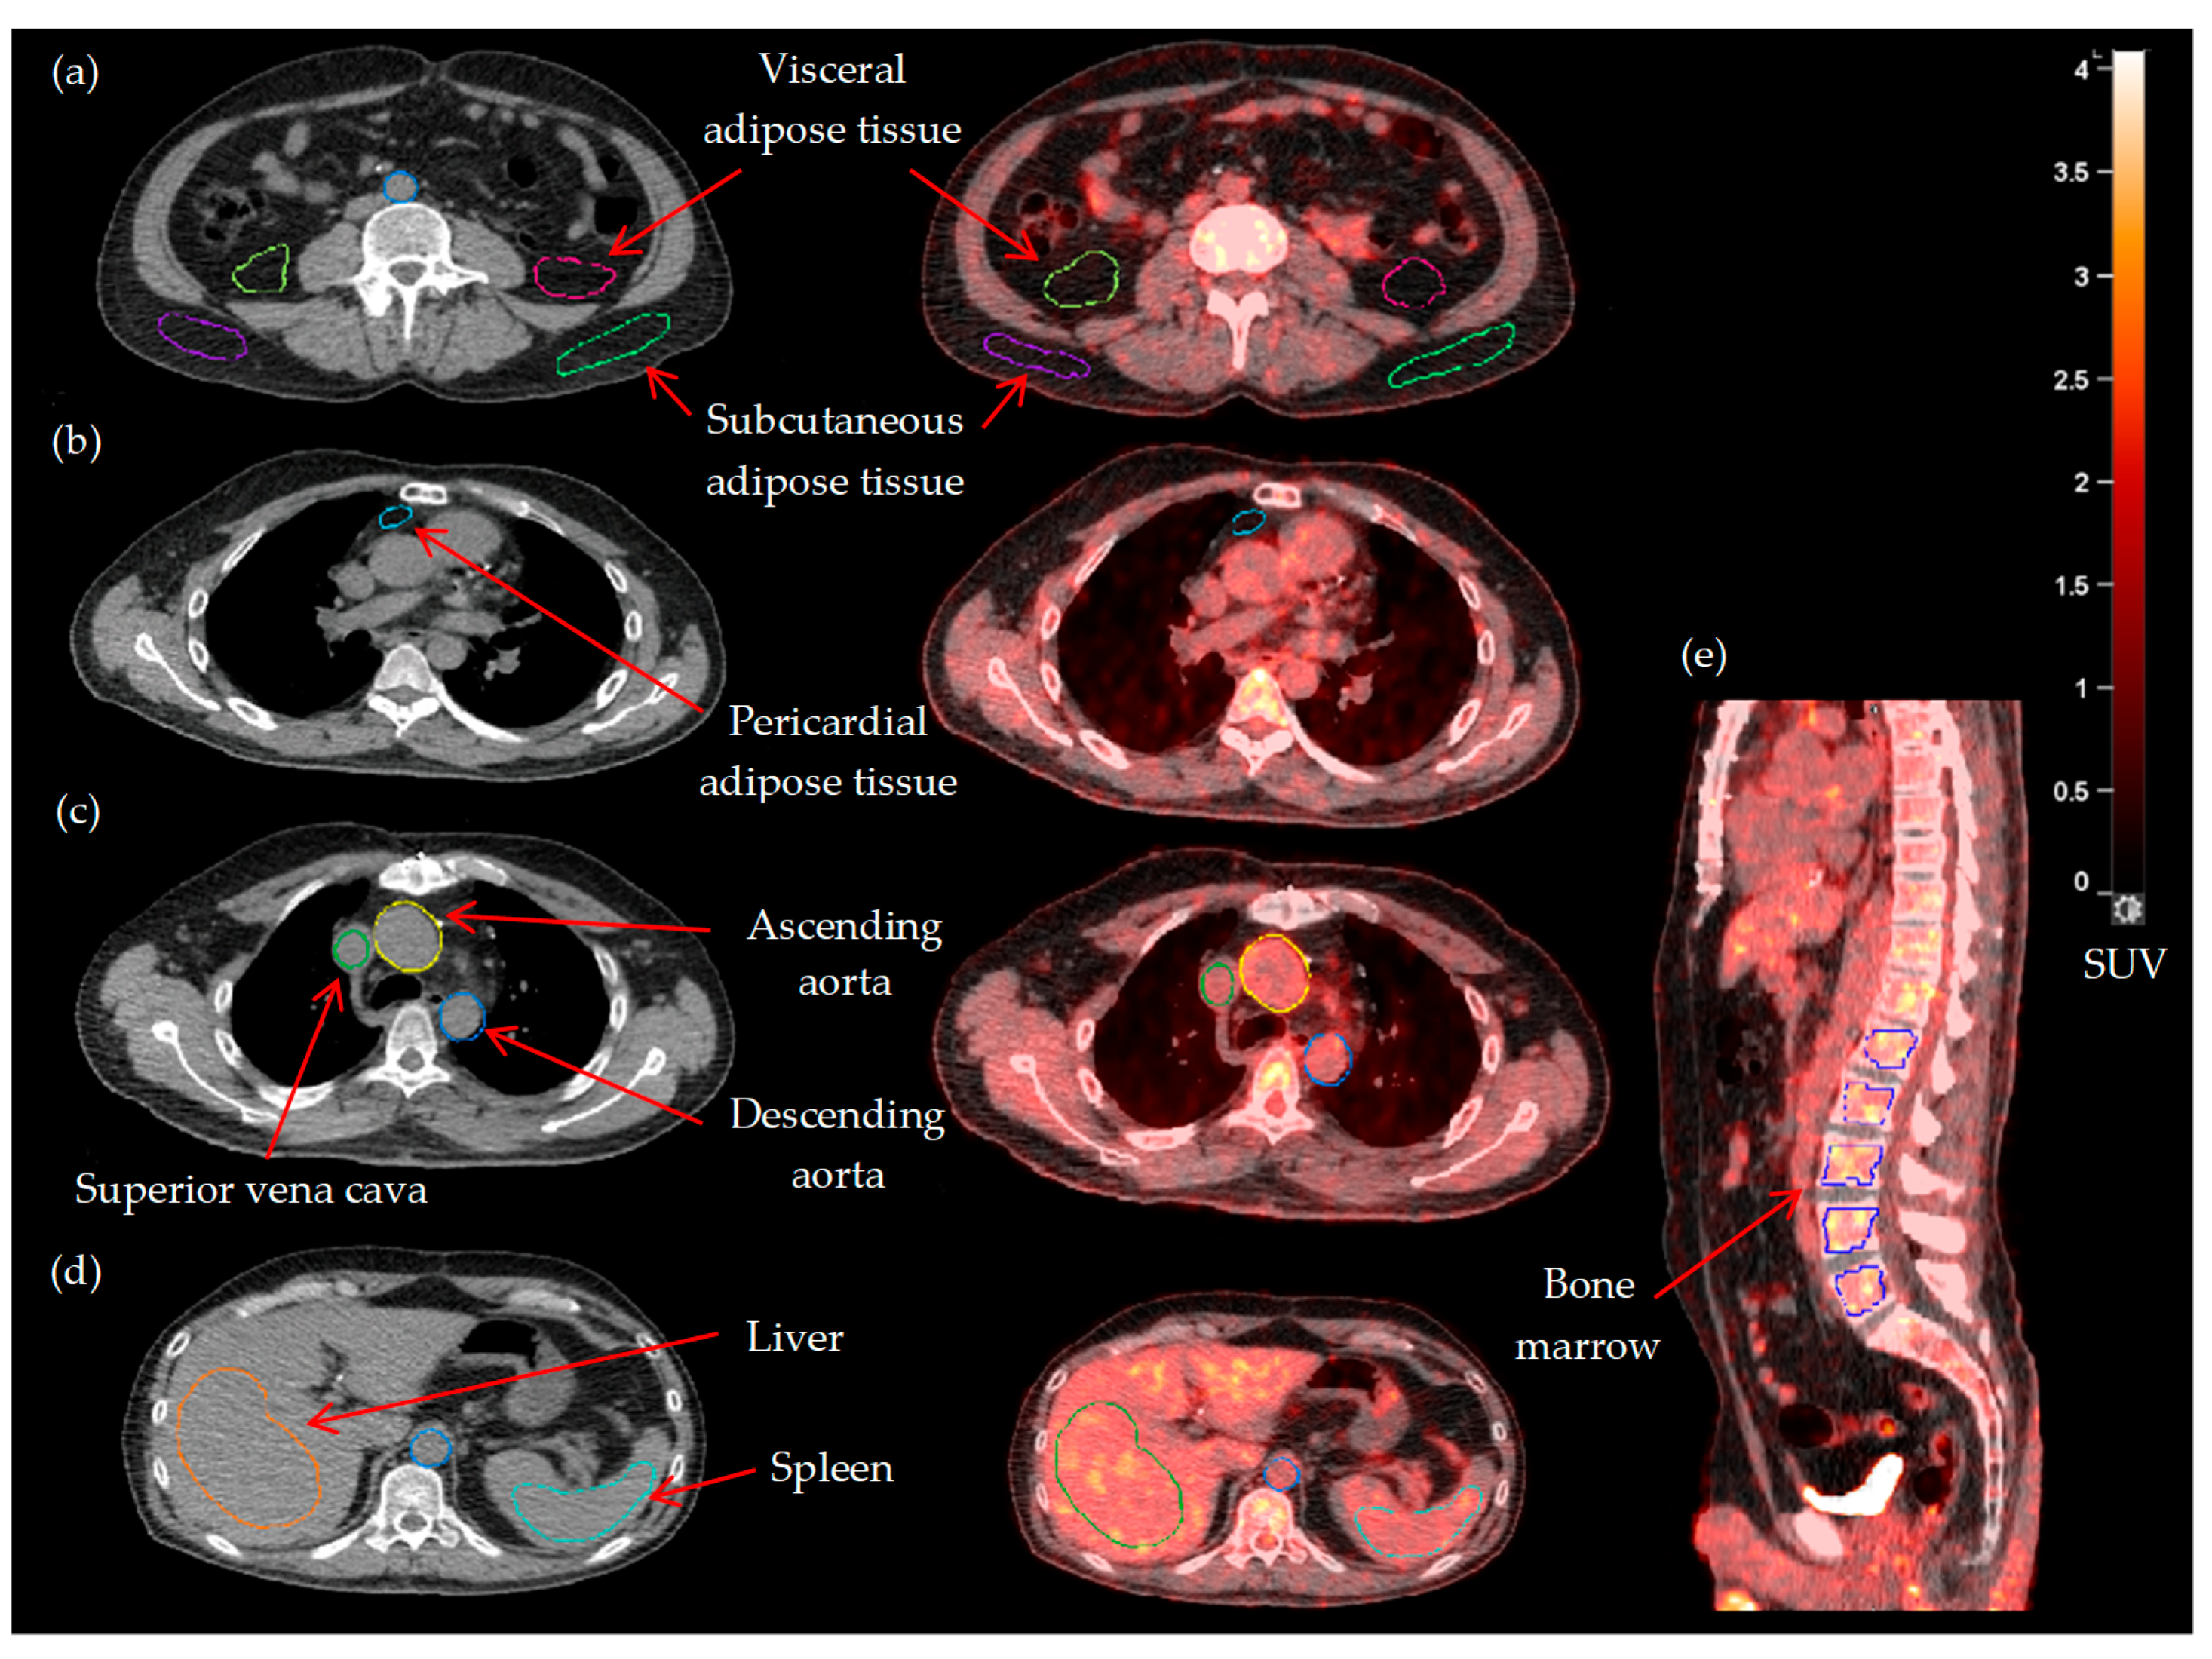

| Entire aorta (TBRmax) | 2.27 ± 0.39 |

| Visceral adipose tissue (TBRmean) | 0.17 (0.15–0.21) |

| Subcutaneous adipose tissue (TBRmean) | 0.13 (0.11–0.16) |

| Pericardial adipose tissue (TBRmean) | 0.34 (0.26–0.52) |

| Spleen (SLRmean) | 0.94 ± 0.10 |

| Bone marrow (BLRmean) | 1.00 ± 0.20 |